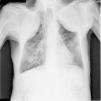

Presentamos el caso de un paciente varón de 87 años, con antecedentes de tuberculosis pulmonar en su juventud, que se trató con colapsoterapia bilateral con aceite (oleotórax)1, que provocó con el desarrollo de los años una alteración ventilatoria restrictiva con insuficiencia respiratoria hipercápnica. Precisó varios ingresos hospitalarios hasta iniciar ventilación no invasora2 durante el sueño. El paciente ha permanecido en seguimiento en nuestras consultas con buen cumplimiento terapéutico y escasas descompensaciones.

La cirugía de la tuberculosis tuvo un gran auge desde finales del siglo XIX hasta mediados del siglo XX, momento en el que el desarrollo de los fármacos antituberculosos y sus combinaciones marginaron estas técnicas (fig. 1).